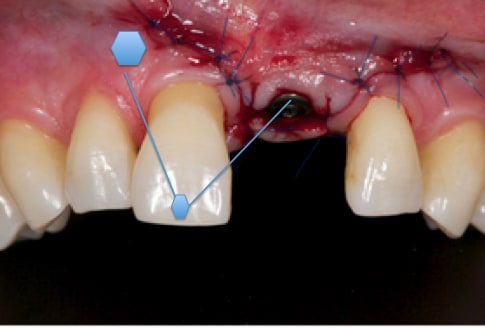

Merci jt2000, seespan et inset pour votre aide. Voici finalement le dispositif que l'on a choisi car je voulais me servir de l'implant comme ancrage.

je vous montrerai l'evolution, favorable ou.... défavorable.

je suis a l'écoute des ortho pour leurs conseils et critiques...

A virskn - Eugenol

B c15bbz - Eugenol

C abqhrm - Eugenol